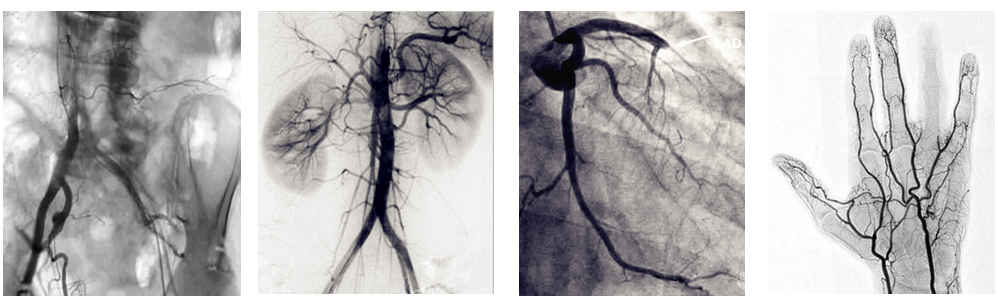

介入c臂机可以把不需要的组织影像删除掉,只保留血管影像。图像清晰,分辨率高,对观察血管病变,血管狭窄的定位测量,诊断及介入治疗提供了真实的立体图像,还具有多种工作模式,灵活方便,满足各种临床需要,为各种介入治疗提供了必备条件。

普爱医疗PLX7100A数字移动式C型臂X射线机是为周边介入治疗而设计的移动式平板介入c臂机,配备新型的非晶硅动态平板探测器,使之成为一款更加贴合介入临床需求的移动式介入设备。下面小编给大家介绍下我公司介入c臂机临床应用及性能特点:

PLX7100A移动式介入c臂机,体积小,剂量低,图像清晰,是广大基层医院介入肿瘤科以及三甲医院专科介入(如肝胆外科、ERCP室、妇科)使用的理想设备。